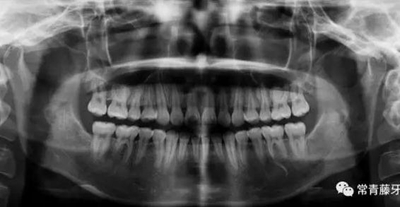

影像學檢查

曲斷顯示38、48阻生;雙側(cè)TMJ髁突頭略不對稱。

曲斷可見牙根基本平行。